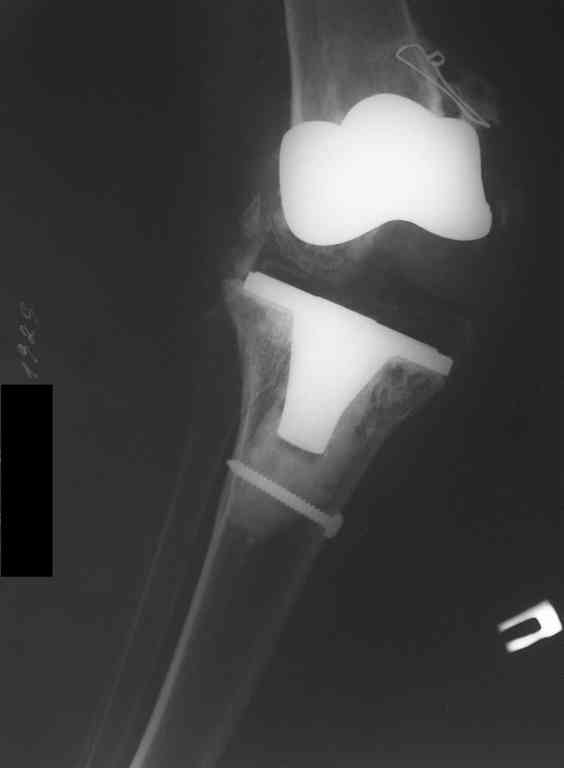

This patient is a 78 y o woman, she has osteoarthritis.3 years ago she had a total right knee replacement (Zimmer LPC).

after she started to walk without a cane,she felt that her knee is (giving way).the clinical knee examination showed medial knee instability and valgus deformation of this knee.2 years ago MCL repair was achieved……and no improvement.A year ago,she had knee replacement for this knee for the second time with bigger-sized implant and no improvement…now she using crutches and knee orthosis. In attachments ,2 monthes ago x-ray images. Any suggestion?